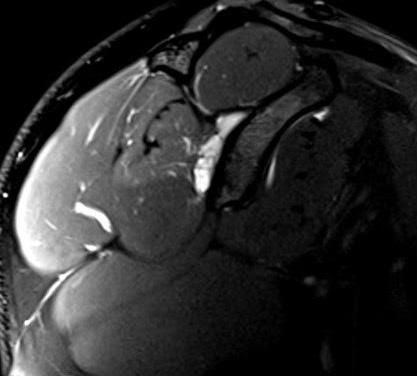

Artroresonancia magnética de hombro derecho con resonador de 1.5T. Se inyectaron 15cc de medio de contraste intraarticular bajo guía ecográfica en el receso articular posterior, obteniendo imágenes multiplanares en secuencias T1-FS, DP-FS y volumétricas T2-me3D.

Figura 1: Secuencia sagital T1-FS: adecuada distensión de la cápsula articular tras la administración directa de medio de contraste bajo guía ecográfica.